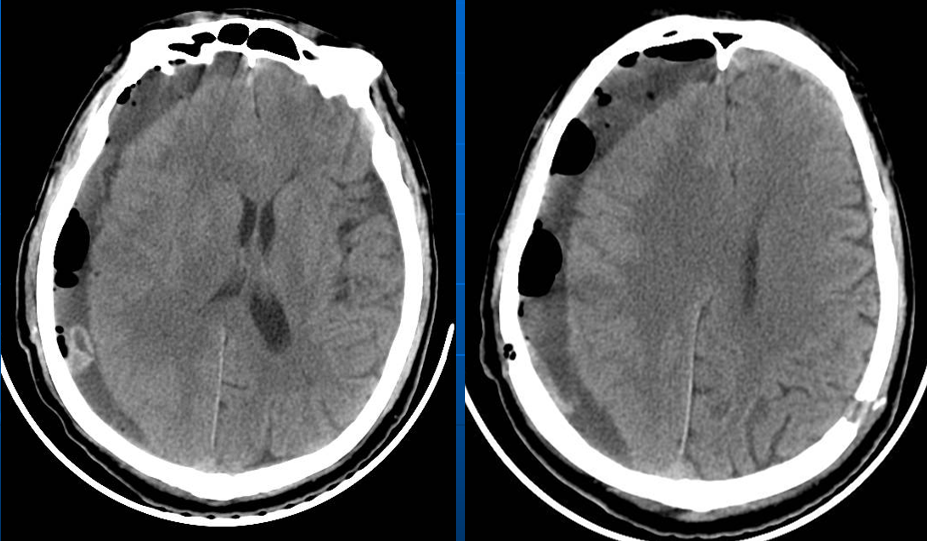

患者约2个月前无明显诱因(否认外伤史)间断出现头痛,头痛为胀痛,左侧较明显,恶心未吐,食欲、睡眠尚可,未予特殊诊治,1个月前患者头痛逐渐加重,思睡,反应略迟钝,行头部CT检查示“慢性硬膜下血肿(双侧)”,于2018年12月15日行颅骨钻孔引流术(左)。术后9天患者恢复良好出院。出院后2周于2019年1月9日患者头痛再次加重,伴有反应迟钝,走路困难,疲乏无力再次就诊,头部CT示“慢性硬膜下血肿(右侧)”,当日再次行颅骨钻孔引流术(右)。术后患者一般状态逐渐好转,无抽搐,无尿便失禁。

2019年1月9日第二次入院

术后情况

术后当日(2019年1月16日)

术后3天(2019年1月18日)

复发可能的危险因素

1. 患者自身特点,如老年、脑萎缩、出血倾向、肝肾疾病、酒精依赖、糖尿病、癫痫、低颅压征(脑室-腹腔分流术后);

2. 与SDH 疾病本身相关因素,如巨大血肿、双侧血肿、血肿腔内有分隔、血肿机化、CT 表现为高/混杂密度;

高龄脑萎缩。

血肿分隔多房。

脑萎缩较明显。

双侧血肿,量较大。